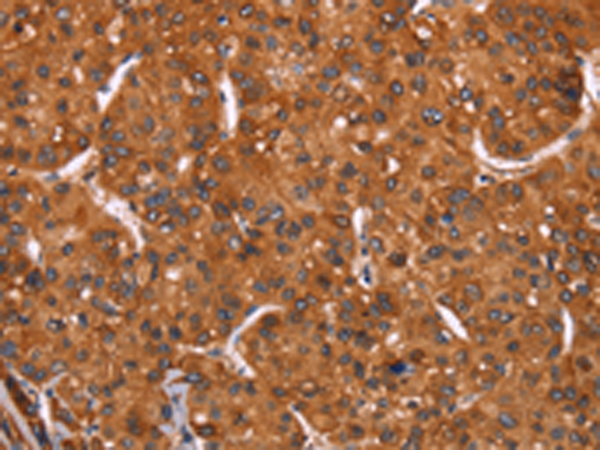

分类: 科研抗体货号: P11855别名: IMPD; RP10; IMPD1; LCA11; sWSS2608应用: WB,IHC反应种属: Human, Mouse, Rat